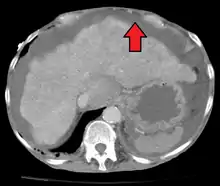

Ultrasound investigation is often performed prior to attempts to remove fluid from the abdomen. This may reveal the size and shape of the abdominal organs, and Doppler studies may show the direction of flow in the portal vein, as well as detecting Budd-Chiari syndrome (thrombosis of the hepatic vein) and portal vein thrombosis. Additionally, the sonographer can make an estimation of the amount of ascitic fluid, and difficult-to-drain ascites may be drained under ultrasound guidance. An abdominal CT scan is a more accurate alternate to reveal abdominal organ structure and morphology.